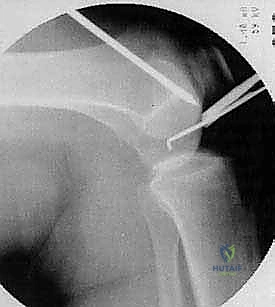

4. التنظير المفصلي التشخيصي (Diagnostic Arthroscopy)

في بعض الحالات المعقدة، قد يكون التشخيص النهائي وتقييم قابلية الشفاء (عن طريق لمس الغضروف بأداة جراحية لتقييم صلابته) لا يتم إلا من خلال المنظار الجراحي. يستخدم الدكتور هطيف كاميرات 4K عالية الدقة لرؤية المفصل من الداخل بوضوح لا مثيل له.